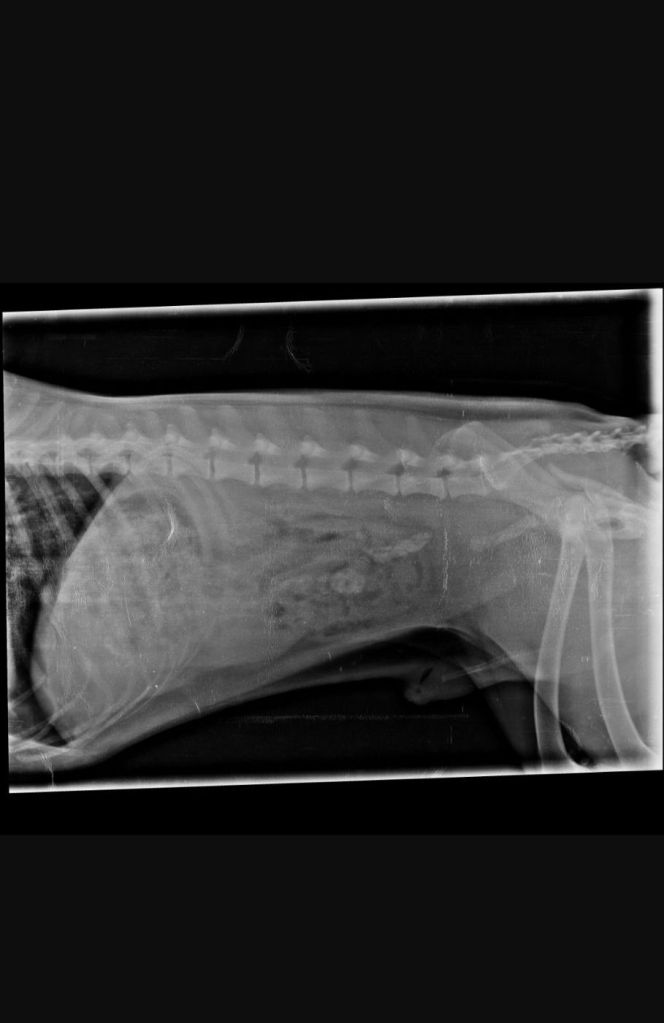

There was a lot of internal and external bleeding that we saw right away…he was screaming in pain.

We had to rush him into an emergency and ensure the vets stabilized him. .. turns out he has a fractured hip and multiple injuries , one even on his penis π which bled so much.

He is still in a lot of pain and hence on heavy medication and sedatives.. we will know more about his injuries once all the swelling subsides…